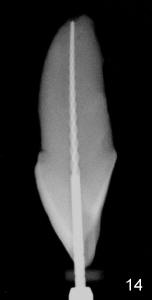

The tooth #8 of a 61-year-old man has obliterated canal probably due to trauma (Fig.1,2 (lateral view)). Initial access shows that the labial portion of the recessed pulpal horn (brown, < in Fig.3 (occlusal view) is not fully exposed, while that the most lingual aspect of the incisal edge (between **) has been removed. Further access appears to be necessary to expose the obliterated pulpal chamber (Fig.7 <) and more of the incisal edge has been violated ( between **). With good exposure, the canal is easily found around the arrowhead (<) in Fig.7. Laterally, the initial file: C6 is straight and slightly labial to the incisal edge (Fig.6). But it is somewhat bent in the front view (Fig.5). After enlargement of the coronal canal with Gates-Glidden files #2 and 3 (Fig.9<), #20 file appears to move distally (<-) and is straighter than the file in Fig.5. Laterally, the #20 file remains without much tension and around the incisal edge (Fig.10). Fig.11 shows occlusal view of the access after application of Gates-Glidden files. Before rotary files, the access is enlarged further both labially and lingually with diamond/carbide endo access burs (Fig.15). Fig.13,14 show 40/.04 file in the canal free without strain. The file seems to move distally further (Fig.13 <-).